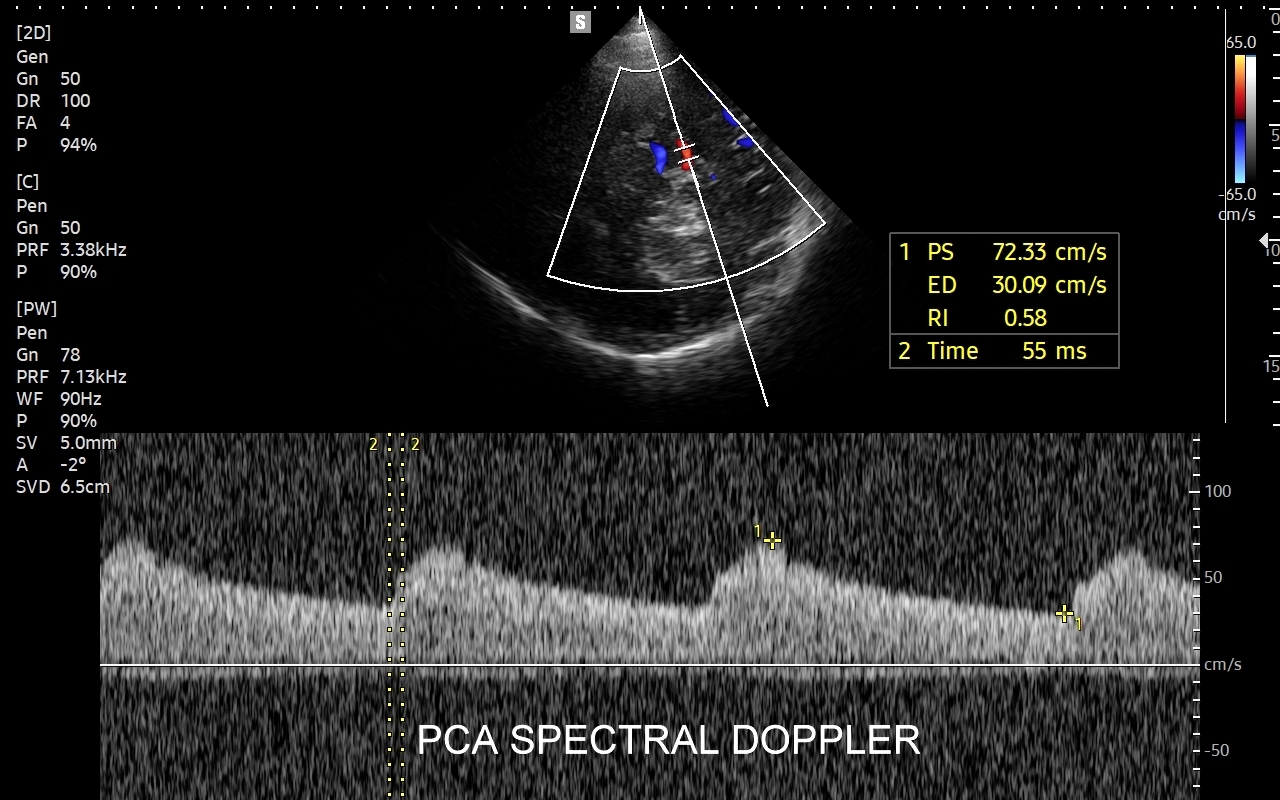

USG TCCD tętnic wewnątrzczaszkowych

Badanie USG Doppler tętnic wewnątrzczaszkowych (ang. TCCD, transcranial color-coded Doppler), nazywane także Dopplerem przezczaszkowym jest naturalnym rozszerzeniem i uzupełnieniem badania dopplerowskiego tętnic dogłowowych zewnątrzczaszkowych. Badanie polega na obrazowaniu przy użyciu dedykowanej sondy poprzez tzw. okno skroniowe czaszki głównych naczyń tętniczych mózgu, tj. koła Willisa, tętnic mózgowych przednich, środkowych i tylnych po obu stronach. Badanie TCCD umożliwia wykrycie wybranych wewnątrzczaszkowych patologii naczyniowych takich jak tętniaki, malformacje naczyniowe, zwężenia i niedrożności poszczególnych tętnic mózgowych, spazm naczyniowy, a także pozwala na ocenę kierunku przepływy krwi w kole Willisa mózgu, co  jest przydatne przy diagnostyce zespołu podkradania lub w ocenie po przebyciu udaru mózgowego.